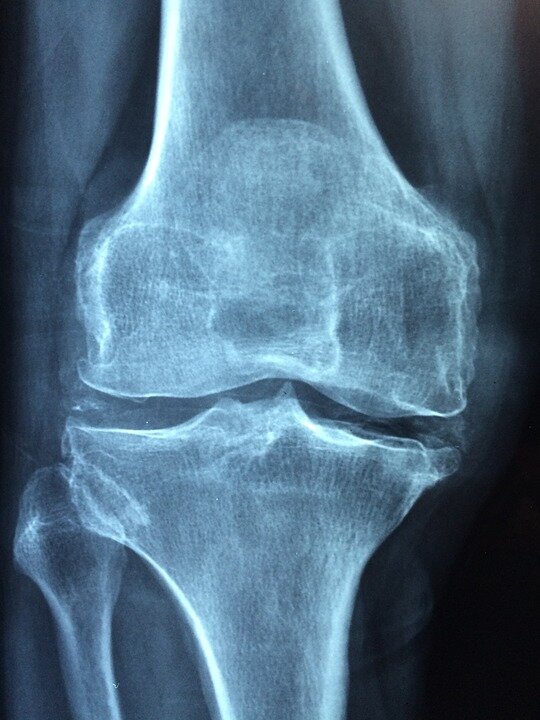

Немного статистики! Только по официальным данным в России насчитывается более 10 миллионов больных артрозом и около 300 тысяч россиян страдают ревматоидным артритом (примерно треть из них имеют тяжелые формы инвалидности). Распространенность артрита и артроза неизменно растет. Так, за период 2001-2005 гг. заболеваемость артрозом выросла на 48%. [1]. Артроз встречается у каждого третьего пациента в возрасте от 45 до 64 лет и у 60–70% – старше 65 лет [2]. По данным ВОЗ, артроз коленных суставов находится на 4-м месте среди основных причин нетрудоспособности у женщин и на 8-м месте у мужчин. На своем опыте и ощущениям это заболевание начинается чуть ли не с детства . В нашем детстве мы часто ходили и долго в резиновых сапогах , не скрою что помню как часто замерзали ноги в них , но дети есть дети как то мы на это мало обращали внимания более того, в 30 градусов мороза играли на улице пока не окоченеем)Но все это потом только в 35 лет начнет сказываться , китайские врачи говорят что если

Немного статистики! Только по официальным данным в России насчитывается более 10 миллионов больных артрозом и около 300 тысяч россиян страдают ревматоидным артритом (примерно треть из них имеют тяжелые формы инвалидности). Распространенность артрита и артроза неизменно растет. Так, за период 2001-2005 гг. заболеваемость артрозом выросла на 48%. [1]. Артроз встречается у каждого третьего пациента в возрасте от 45 до 64 лет и у 60–70% – старше 65 лет [2]. По данным ВОЗ, артроз коленных суставов находится на 4-м месте среди основных причин нетрудоспособности у женщин и на 8-м месте у мужчин.